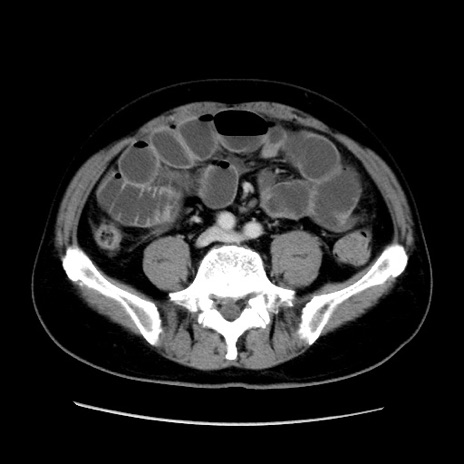

症例16(横断像)

【症例】 70歳代男性

【主訴】 腹痛、嘔吐

【現病歴】 約1ヶ月前より間欠的に腹痛と嘔吐あり、当院消化器内科を受診したところCTで多発する肝臓のLDAを指摘され、精査中であった。以降は消化器症状は安定していたが、2日前より嘔気と腹痛があり、同日より排便・排ガスが消失した。改善認めず、 本日、救急外来を受診した。

【身体所見】意識清明・会話良好、BT 36.3℃、BP 127/80mmHg、 P 80bpm、腹部:膨満あり、平坦・軟、上腹部正中および下腹部正中に圧痛あり、反跳痛なし、筋性防御なし。

【データ】WBC 7200、CRP 0.77